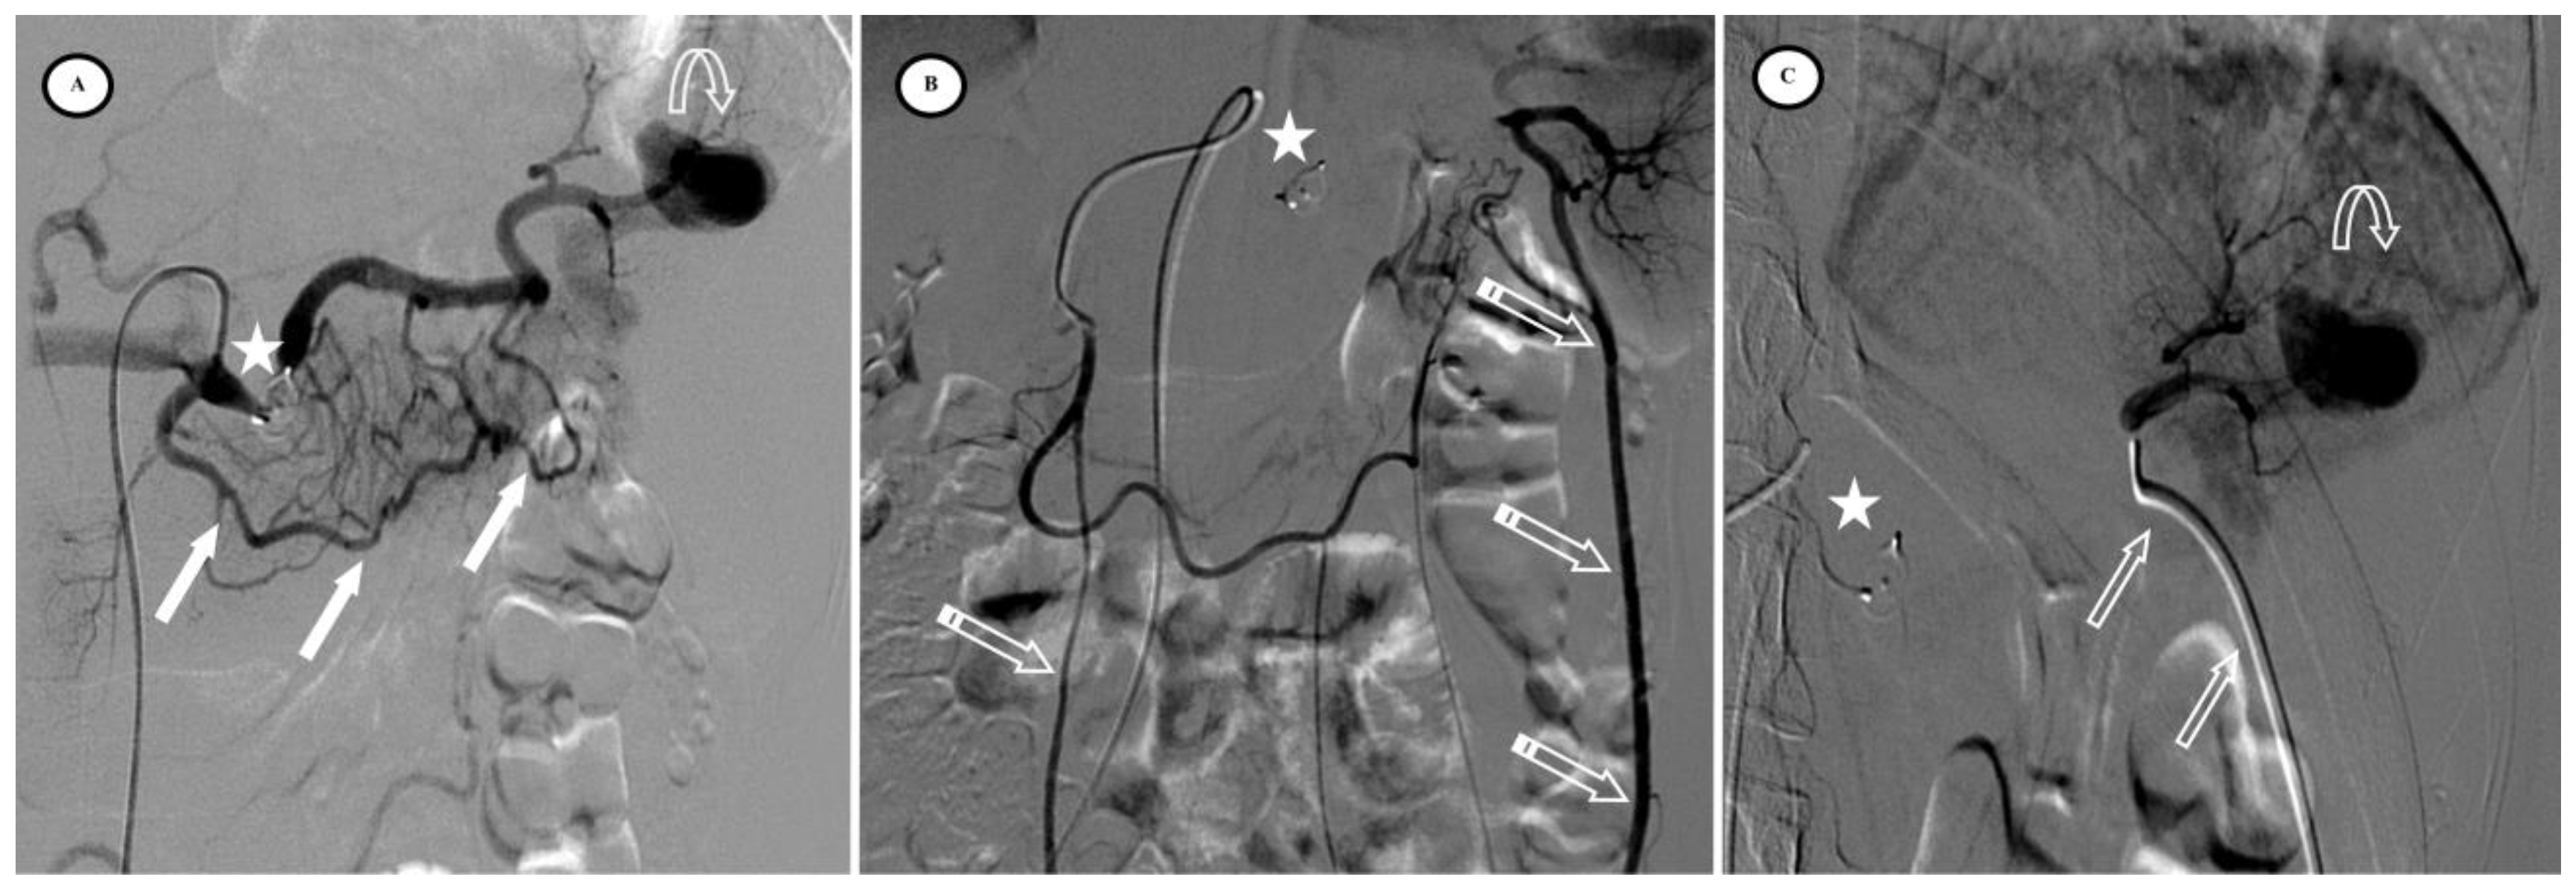

Figure 4.

Secondary pseudoaneurysm formation 6 days after preventive proximal splenic artery embolization (PPSAE). (A) shows PPSAE with a vascular plug (star) and the development of collateral circulation (arrows) alongside pseudoaneurysm formation (curved arrow). (B) displays the dominant collateral circulation via the gastroepiploic artery (striped arrows). (C) Microcatheter selection of the gastroepiploic artery for distal embolization (blank arrows).

Figure 5.

Secondary arteriovenous (AV) fistula development 30 days after preventive proximal splenic artery embolization (PPSAE). (A) shows PPSAE using Penumbra occlusion device (star), the subsequent development of collateral circulation mainly through the dorsal pancreatic artery and the great pancreatic artery (blank arrows), and the secondary AV fistula (arrow). (B) illustrates the distal microcatheter selection (striped arrow) through radial access. (C) shows microcoil embolization (blank star) with satisfying angiographic results.